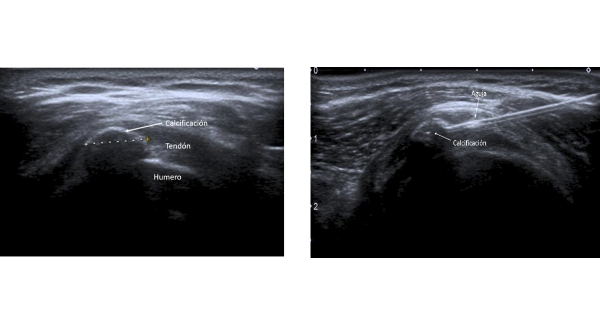

La ecografía de la izquierda muestra una tendinitis calcificante en el hombro y la de la izquierda, la intervención guiada por ecografía usando una aguja para aspirarla y eliminarla

Hasta hace pocos años, el único tratamiento de esta patología era el uso de antiinflamatorios y, en casos más graves, la cirugía por artroscopia, que no siempre es resolutiva. En la actualidad, las técnicas de imagen como la ecografía, permiten eliminar estas calcificaciones con intervenciones no invasivas que consisten en la introducción de una aguja en la calcificación para aspirarla y eliminarla. La ecografía permite ver a tiempo real el procedimiento y alcanzar con la máxima precisión la calcificación, permitiendo su aspiración.